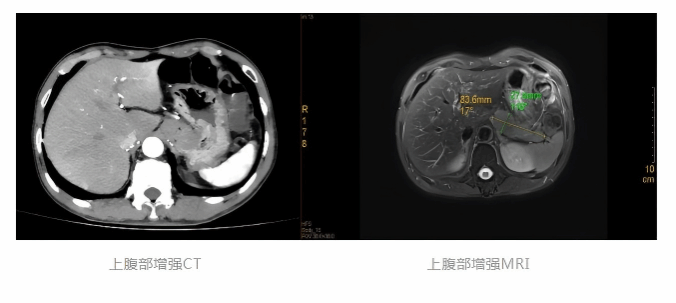

入院后,医疗团队迅速为徐先生完善相关检查,先后完成腹部增强CT、腹部增强MRI及超声胃镜等精准评估项目。影像检查结果清晰提示:患者胃底贲门部存在一巨大外生型肿块,考虑平滑肌瘤或胃间质瘤可能性大。

在各学科的密切配合下,手术顺利开展。消化内科内镜团队凭借精湛的操作技术,通过天然消化道腔道建立黏膜下隧道,精准定位并完整切除肿瘤,肿物大小约30mm×80mm。整个手术过程出血少、创伤小,患者体表无任何手术切口,完全契合“微创无痕”的诊疗理念。